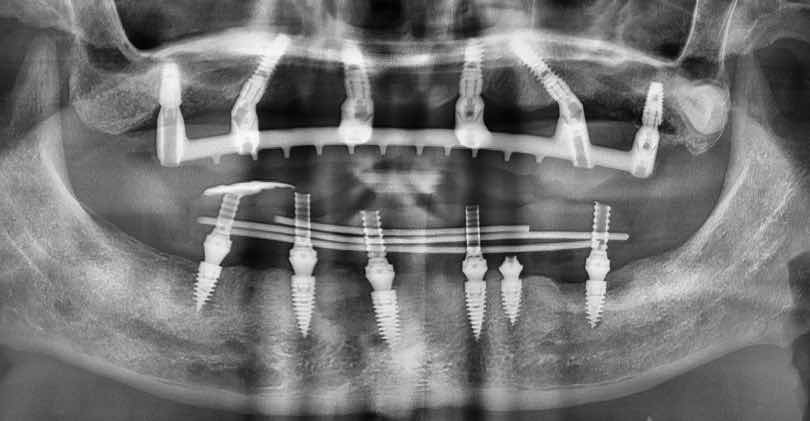

上顎是三年前植入的傳統式all-on-6,當初植入後能立即的底氣在於最初始all on 4理念的傾斜植體,15mm以上植體,並將上卡在前顎區與鼻竇腔與犬齒區最硬的骨質部位,後面兩個正常植體是順便鼻竇增高,但並未立即負重,原則上是做為備胎(避免有任何一顆all on4 失敗),在使用了快三年後,病人決定下顎也換成all on 6!

剛好以色列廠商給予了一些他們新型態的植體試用,這款植體的特色在於容易獲得穩定度(不需要植特別長的植體),而且在即拔即種的情況下也可獲得絕佳穩定度,10-13mm植體,代表手術創傷較小,特殊植體型態,減少手術流程,搭配口內焊接(將植體連一起增加穩定度),有可能改變即刻負重的流程!